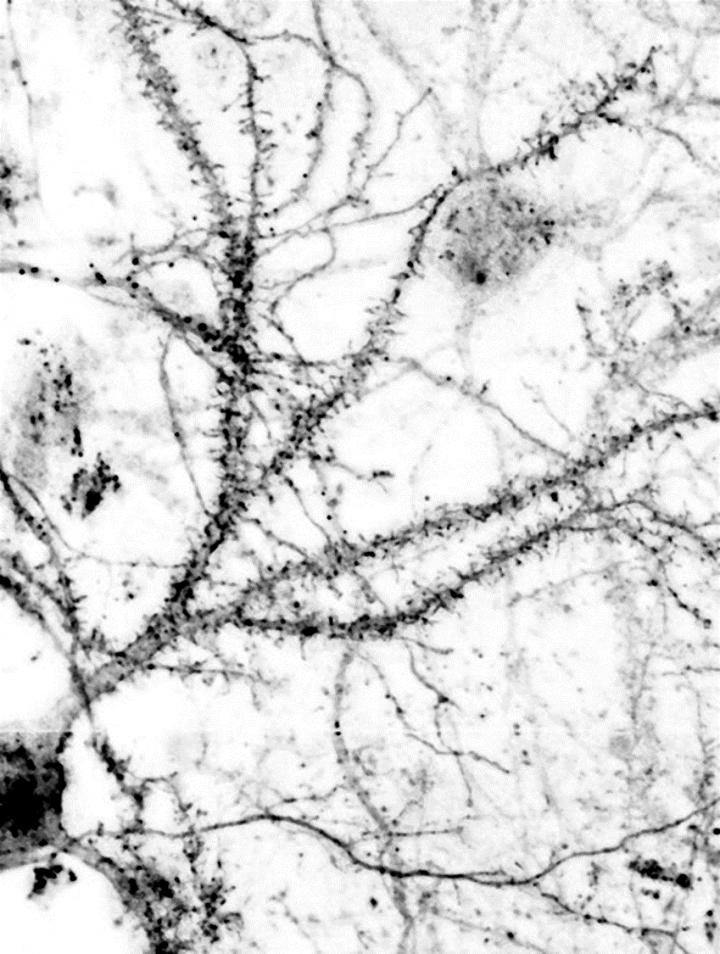

Neuropathic pain is the chronic, pathological pain that continues even when the cause of pain is removed. Causes include damage to nerve cells and medicines used to treat cancer. A collaboration between research groups from Indiana University in Bloomington, USA and Turku Centre for Biotechnology in Finland has discovered a novel therapeutic that appears to interrupt the signaling cascades in the body required for multiple forms of neuropathic pain.

Prior to this study, researchers were aware that pathological pain is triggered by a biological pathway that is activated by binding of the excitatory transmitter glutamate to receptors called NMDARs. This process then triggers activation of an enzyme neuronal nitric oxide synthase (nNOS) that generates nitric oxide gas that plays a role in aberrant pain sensation. However, experimental drugs designed to block either the NMDAR receptor or the nNOS enzyme can cause intolerable side effects, such as memory impairment and motor dysfunction.

The team in the University of Turku in Finland was able to design the molecule after discovering that a protein, NOS1AP, that is downstream of nNOS, triggers several biological pathways that are associated with abnormal glutamate signaling, including neuropathic pain.